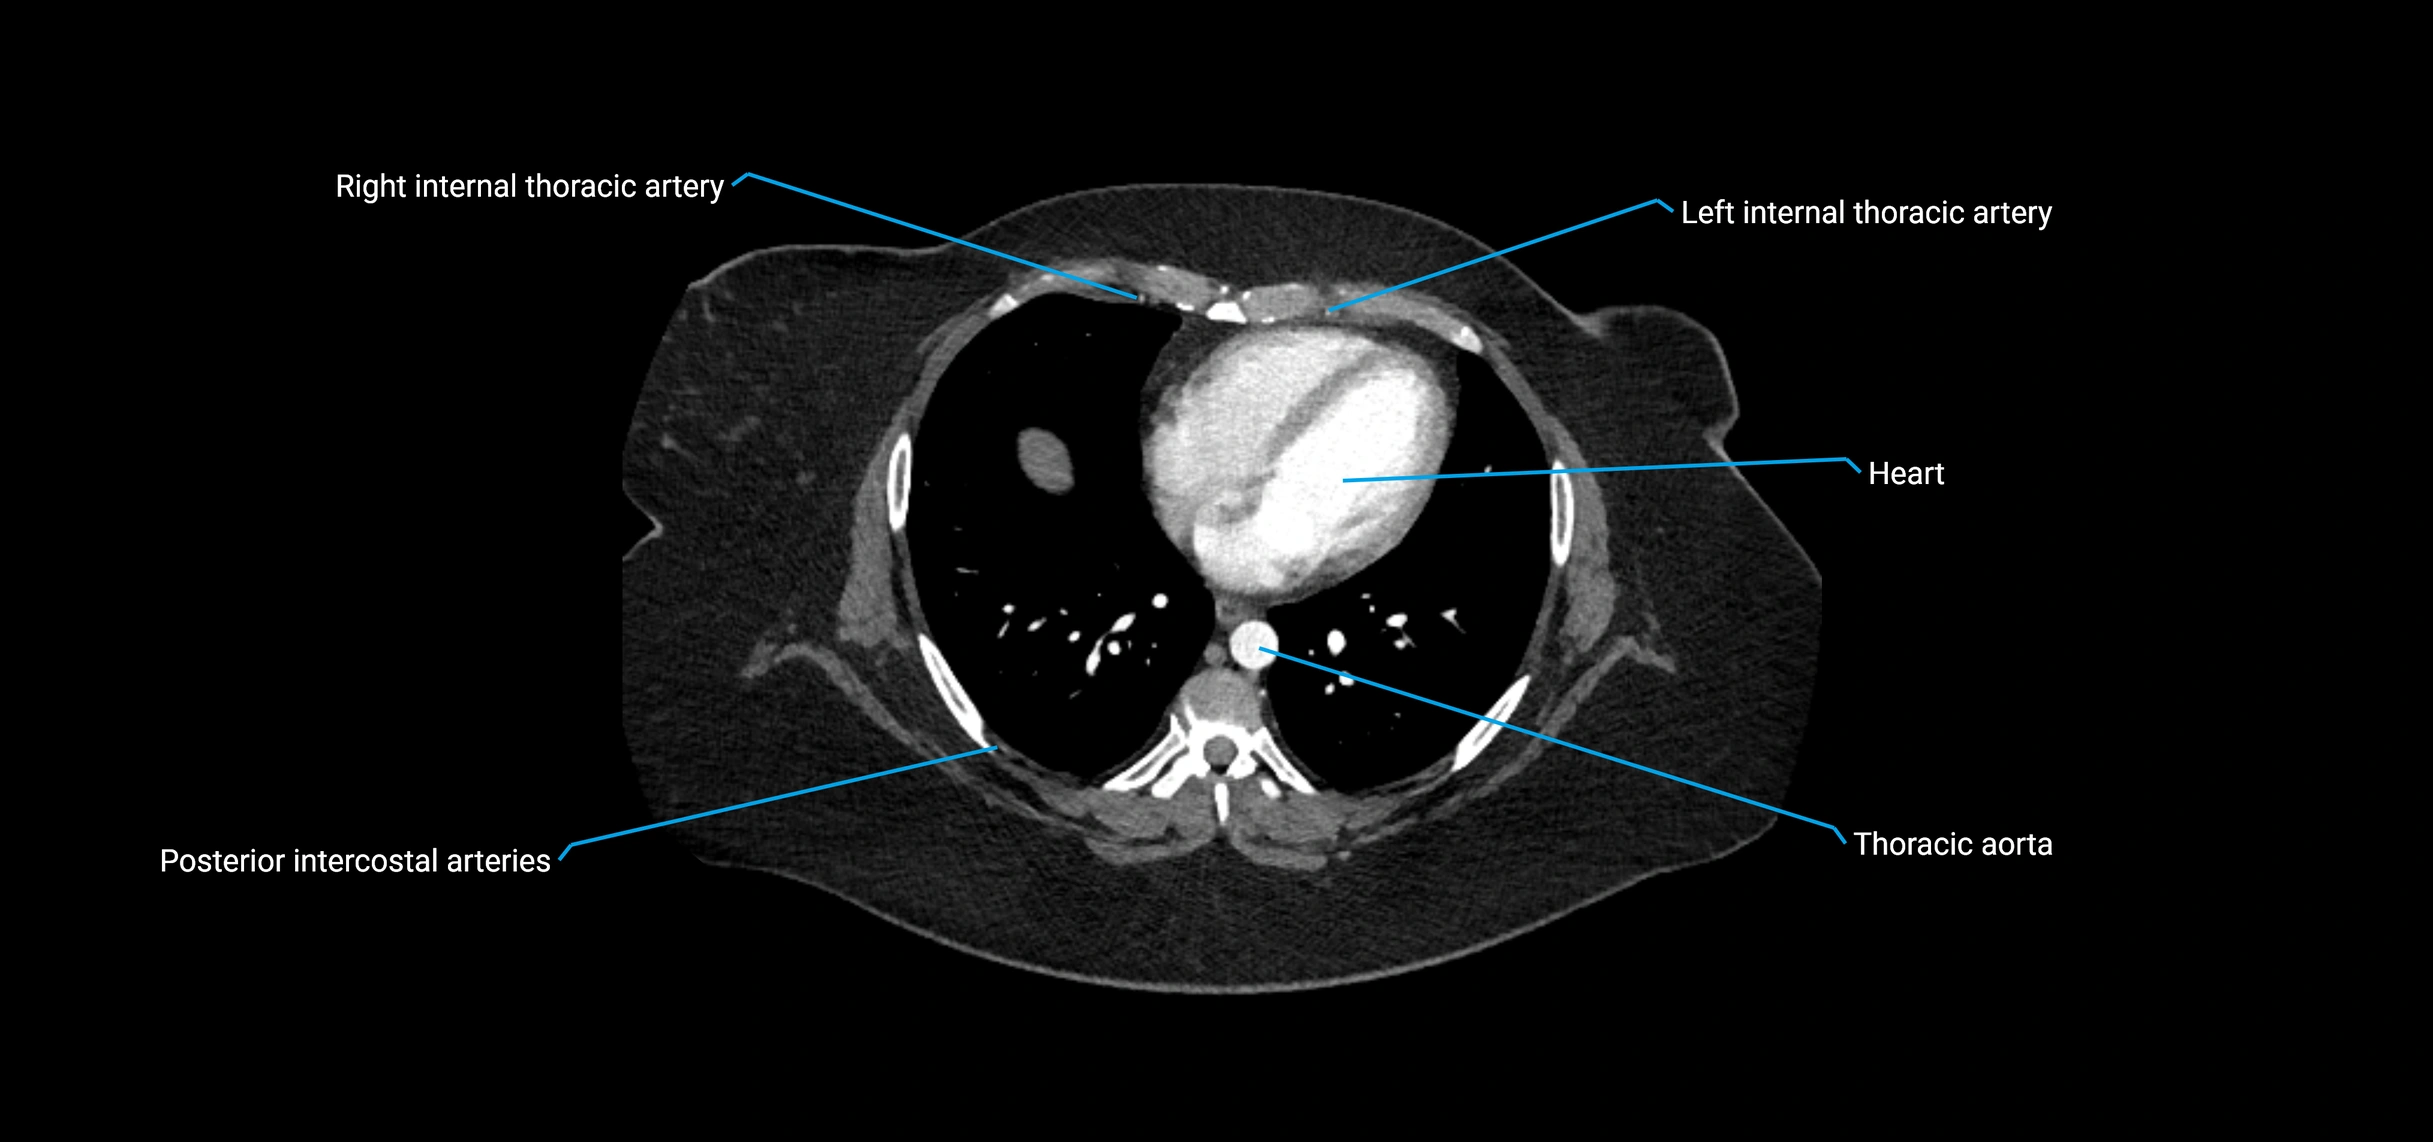

CT Appearance

Non-contrast CT:

• Appears as a tubular soft tissue structure anterior to vertebral bodies

• Calcified atherosclerotic plaques appear as hyperdense foci along the wall

• Useful for screening abdominal aortic aneurysm (AAA) size and mural calcification

Contrast-enhanced CT (CTA):

• Gold standard for abdominal aortic imaging

• Provides excellent detail of lumen, wall, aneurysm, thrombus, and branch vessels

• Multiplanar and 3D reconstructions help in aneurysm measurement, stent graft planning, and dissection evaluation

• Detects acute rupture, traumatic injury, or occlusion with high sensitivity

CT images

image